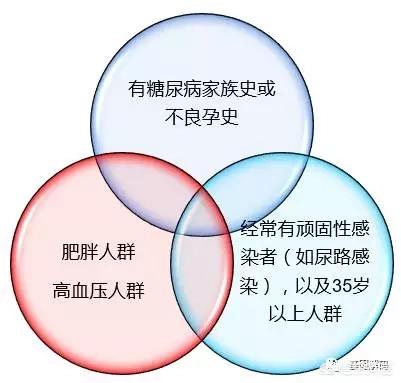

Les futures mères qui sont obèses, plus âgées, qui ont des antécédents familiaux de diabète ou qui ont accouché d'un bébé pesant plus de 4 kg courent un risque élevé de développer un diabète gestationnel.

Des études ont montré que des antécédents familiaux de diabète constituent un facteur de risque de diabète gestationnel, l'incidence du diabète gestationnel étant 1,55 fois plus élevée chez les femmes ayant des antécédents familiaux de diabète que chez celles n'ayant pas d'antécédents familiaux de diabète, et 2,89 fois plus élevée chez les femmes ayant des antécédents familiaux de diabète chez un parent du premier degré. Le risque de diabète gestationnel chez les femmes enceintes âgées de 40 ans et plus est 8,2 fois plus élevé que chez celles âgées de 20 à 30 ans. En outre, l'obésité est un facteur important de diabète gestationnel.

5Principale population testée